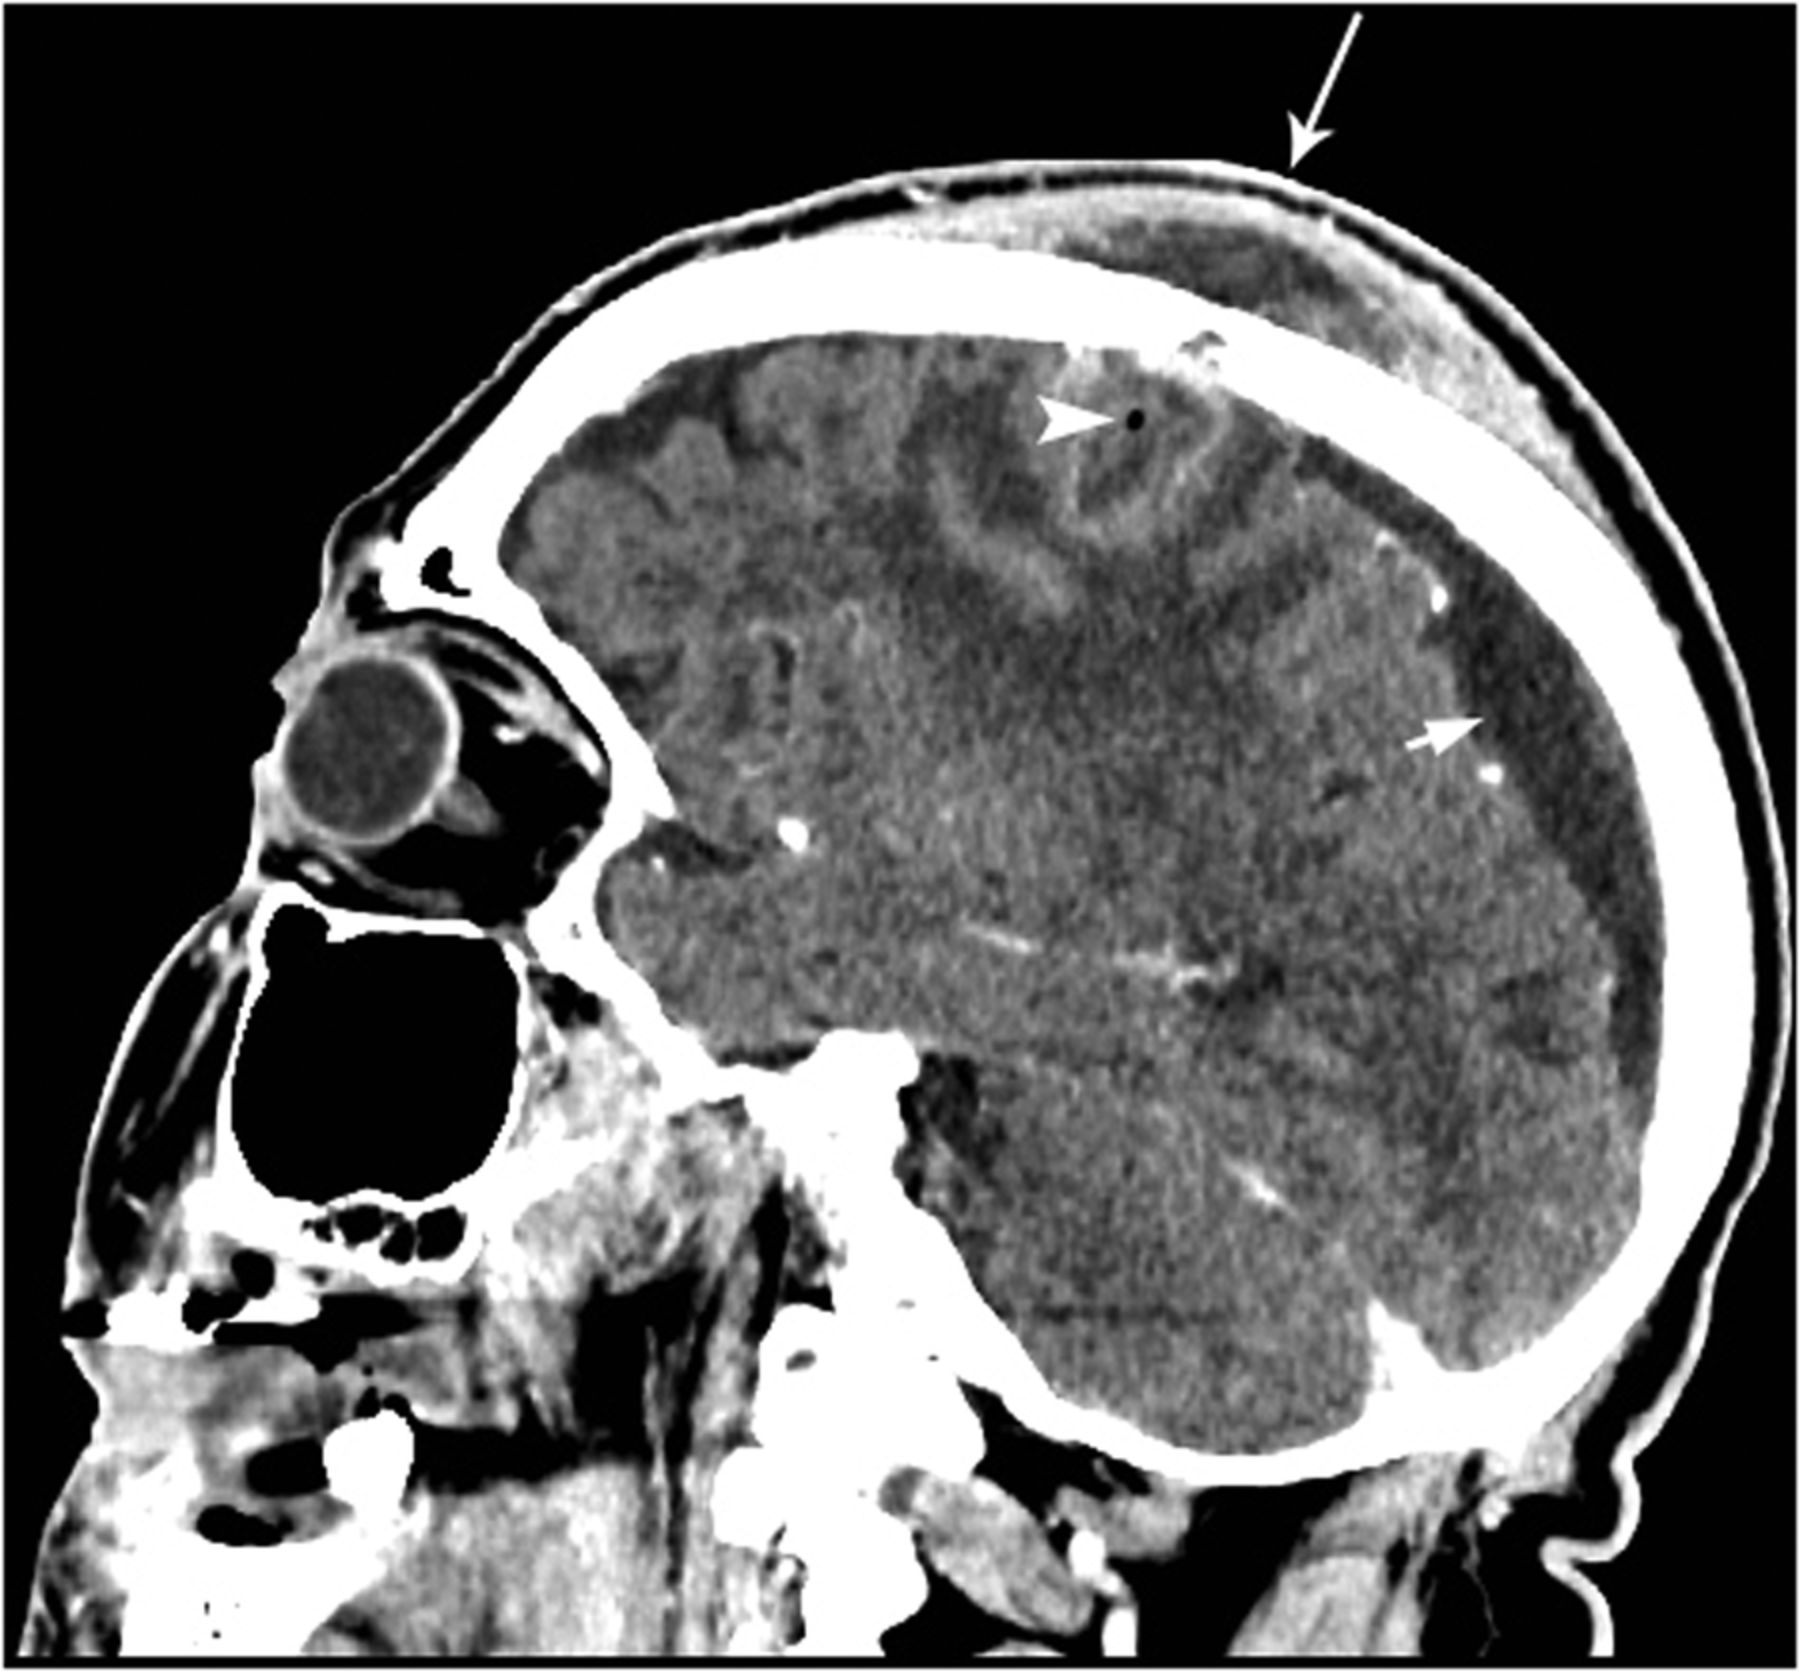

Cerebral Arterial Air Embolism In A Child After Intraosseous

Case Of A Cerebral Abscess Caused By Porphyromonas Gingivalis In A